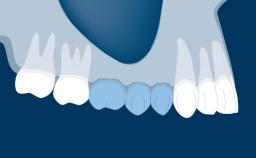

Fixed vs. Removable Prosthodontics for Restoring the Edentulous Maxilla

Fixed and removable prosthodontic implant therapy for restoration of the edentulous maxilla is both complex and challenging. Careful assessment and planning is needed in each individual case to explore whether a fixed or a removable solution will be the more suitable to satisfy the patient’s preference for optimal esthetics, phonetics, comfort and function. This Learning Pathway explores the prosthodontically driven treatment planning based on structured assessment, considered diagnosis and practical application in clinical case examples.